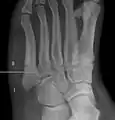

Pseudo-Jones fracture

Other proximal fifth metatarsal fractures exist, although they are not as problematic as a Jones fracture. If the fracture enters the intermetatarsal joint, it is a Jones fracture. If, however, it enters the tarsometatarsal joint, then it is likely an avulsion fracture caused by pull from the fibularis brevis tendon. An avulsion fracture at the base of the fifth metatarsal is sometimes called a "dancer's fracture" or a "pseudo Jones fracture", and usually responds readily to non-operative treatment.[18] The X-ray appearance of the developmental "apophysis" in this area may have some resemblance of a fracture, but is not a fracture; it is the secondary ossification center of the metatarsal bone. It is a normal finding that occurs at this site in adolescents.[19] If an injury to that area has occurred, the physician is often able to interpret certain radiographic clues to make the differentiation. An avulsion fracture at this location is typically extra-articular and oriented transversally as compared to the longitudinal orientation of an unfused apophysis.[19]